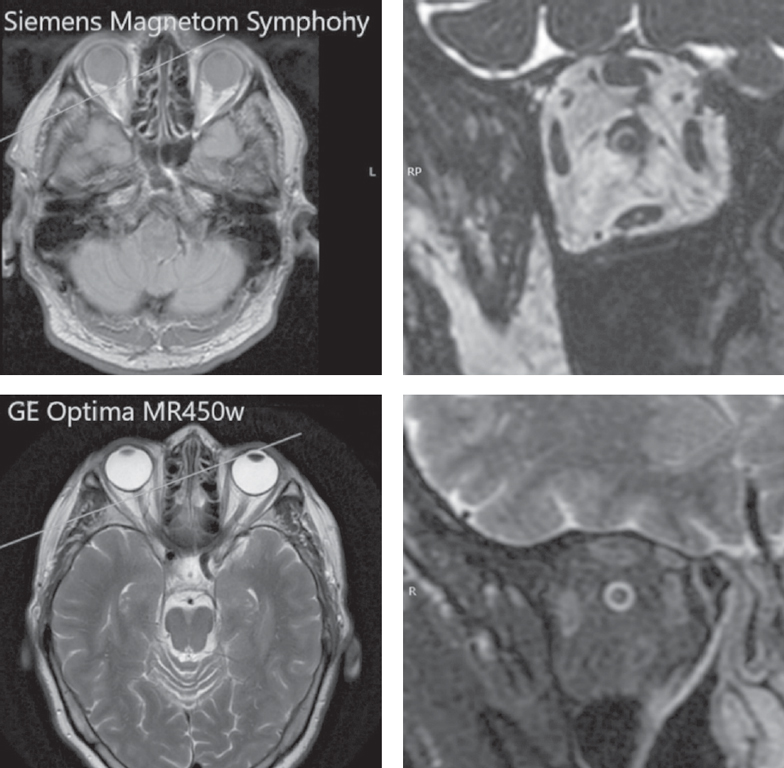

In this study, we used a more modern magnetic resonance imager GE Optima MR450w (USA) with a magnetic field induction of 1.5 T, which enables us to obtain T2 IDEAL pulse sequences with a slice thickness of 1 mm without inter-slice spacing (Table 2).

The IDEAL T2 pulse train suppresses chemical shift artifacts in images of hard-to-reach anatomical structures such as eye sockets. When using this program, 4 different contrast images are generated per one data collection (water, adipose tissue in phase and antiphase). Reliable uniform suppression of the signal from adipose tissue enables to more clearly visualize the perineural cerebrospinal fluid spaces of the ON against the hypointense intraorbital adipose tissue and to avoid repeated fat suppressed scanning. Thus, the T2 IDEAL pulse sequence in the study protocol turned out to be preferable because it enabled us to replace the 3D CISS and turbo-spin-echo with fat suppression sequences that we used in our previous study on a Siemens Magnetom Symphony tomograph, which reduced high-quality imaging scan time (Fig. 4).

Fig. 4. Comparison of cross-sectional slices of the optic nerve obtained with MRI Siemens Magnetom Symphony and MRI GE Optima MR450w

Рис. 4. Сравнение изображений поперечных срезов зрительного нерва, полученных при помощи магнитно-резонансных томографов Siemens Magnetom Symphony и GE Optima MR450w